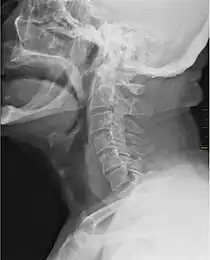

![]() Imagine cu raze X reprezentând gâtlejul (partea închisă la culoare din fața spinării) | |